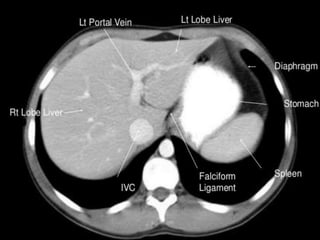

CT cross sectional

anatomy.